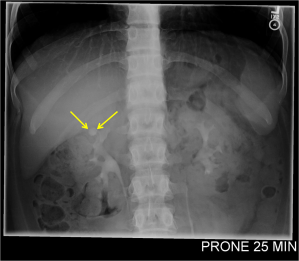

History: 16 year old female with recurrent flank pain.

This is the appearance of a calyceal diverticulum, which is a small outpouching or eventration of a calyx into the renal parenchyma. They are usually connected by a narrow channel to the renal pelvis, as seen in the IVP image above. A calyceal diverticulum can be complicated by renal colic (renal stone), which was the cause of recurrent flank pain in this patient. Occasionally, milk of calcium can precipitate or layer within the calyceal diverticulum and mimic a renal stone. Most commonly, a calyceal diverticulum is incidentally discovered as they are typically asymptomatic.